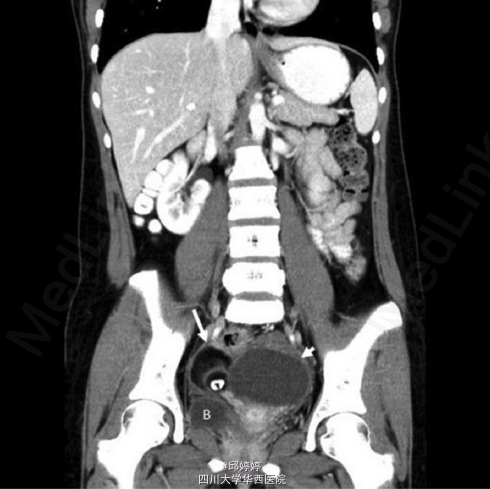

患者,女,20岁,右侧卵巢复发性成熟畸胎瘤伴CA-125增高,曾有两次手术史,第二次术后3年,出现双侧卵巢畸胎瘤。患者主要的临床表现为:间歇性腹痛,痛经,经期延长。第一次手术后一年,腹部超声检查发现(图1 示)患者右侧卵巢有一大小约4.3*3.7cm的高回声肿块,边界清晰,形态类似畸胎瘤,邻近子宫。第二次术后3年,患者再次出现腹痛,痛经等症状,增强CT检查发现(图2 示):左侧附件较大的异质性肿块,右侧附件高密度肿块。术后组织病理学检查确认为双侧附件成熟畸胎瘤,瘤体含脂质,角质,毛发等成分。 讨论:卵巢成熟畸胎瘤是一种良性肿瘤,且较为常见,但像本例这种双侧附件畸胎瘤且多次复发的病例是十分少见的。常规检查及术后超声随访监测对于这种复发性病例是十分必要的。 引自:Chang CF, Lin CK. BMC Womens Health. 2014 Apr 13;14:57